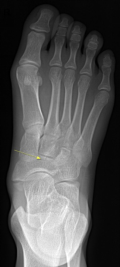

痛风

嘌呤代谢紊乱,以体液、血液中尿酸增加及尿酸盐沉着于各种间叶组织内引起炎症反应

好发于男性,发病高峰40-60岁

以第1跖趾关节最为多见

早期周围软组织肿胀,出现局限骨质硬化,晚期关节面边缘出现囊状、穿凿状骨质缺损,关节间隙可变窄,关节面不光整,晚期骨赘形成可使骨端增大

68Y,M